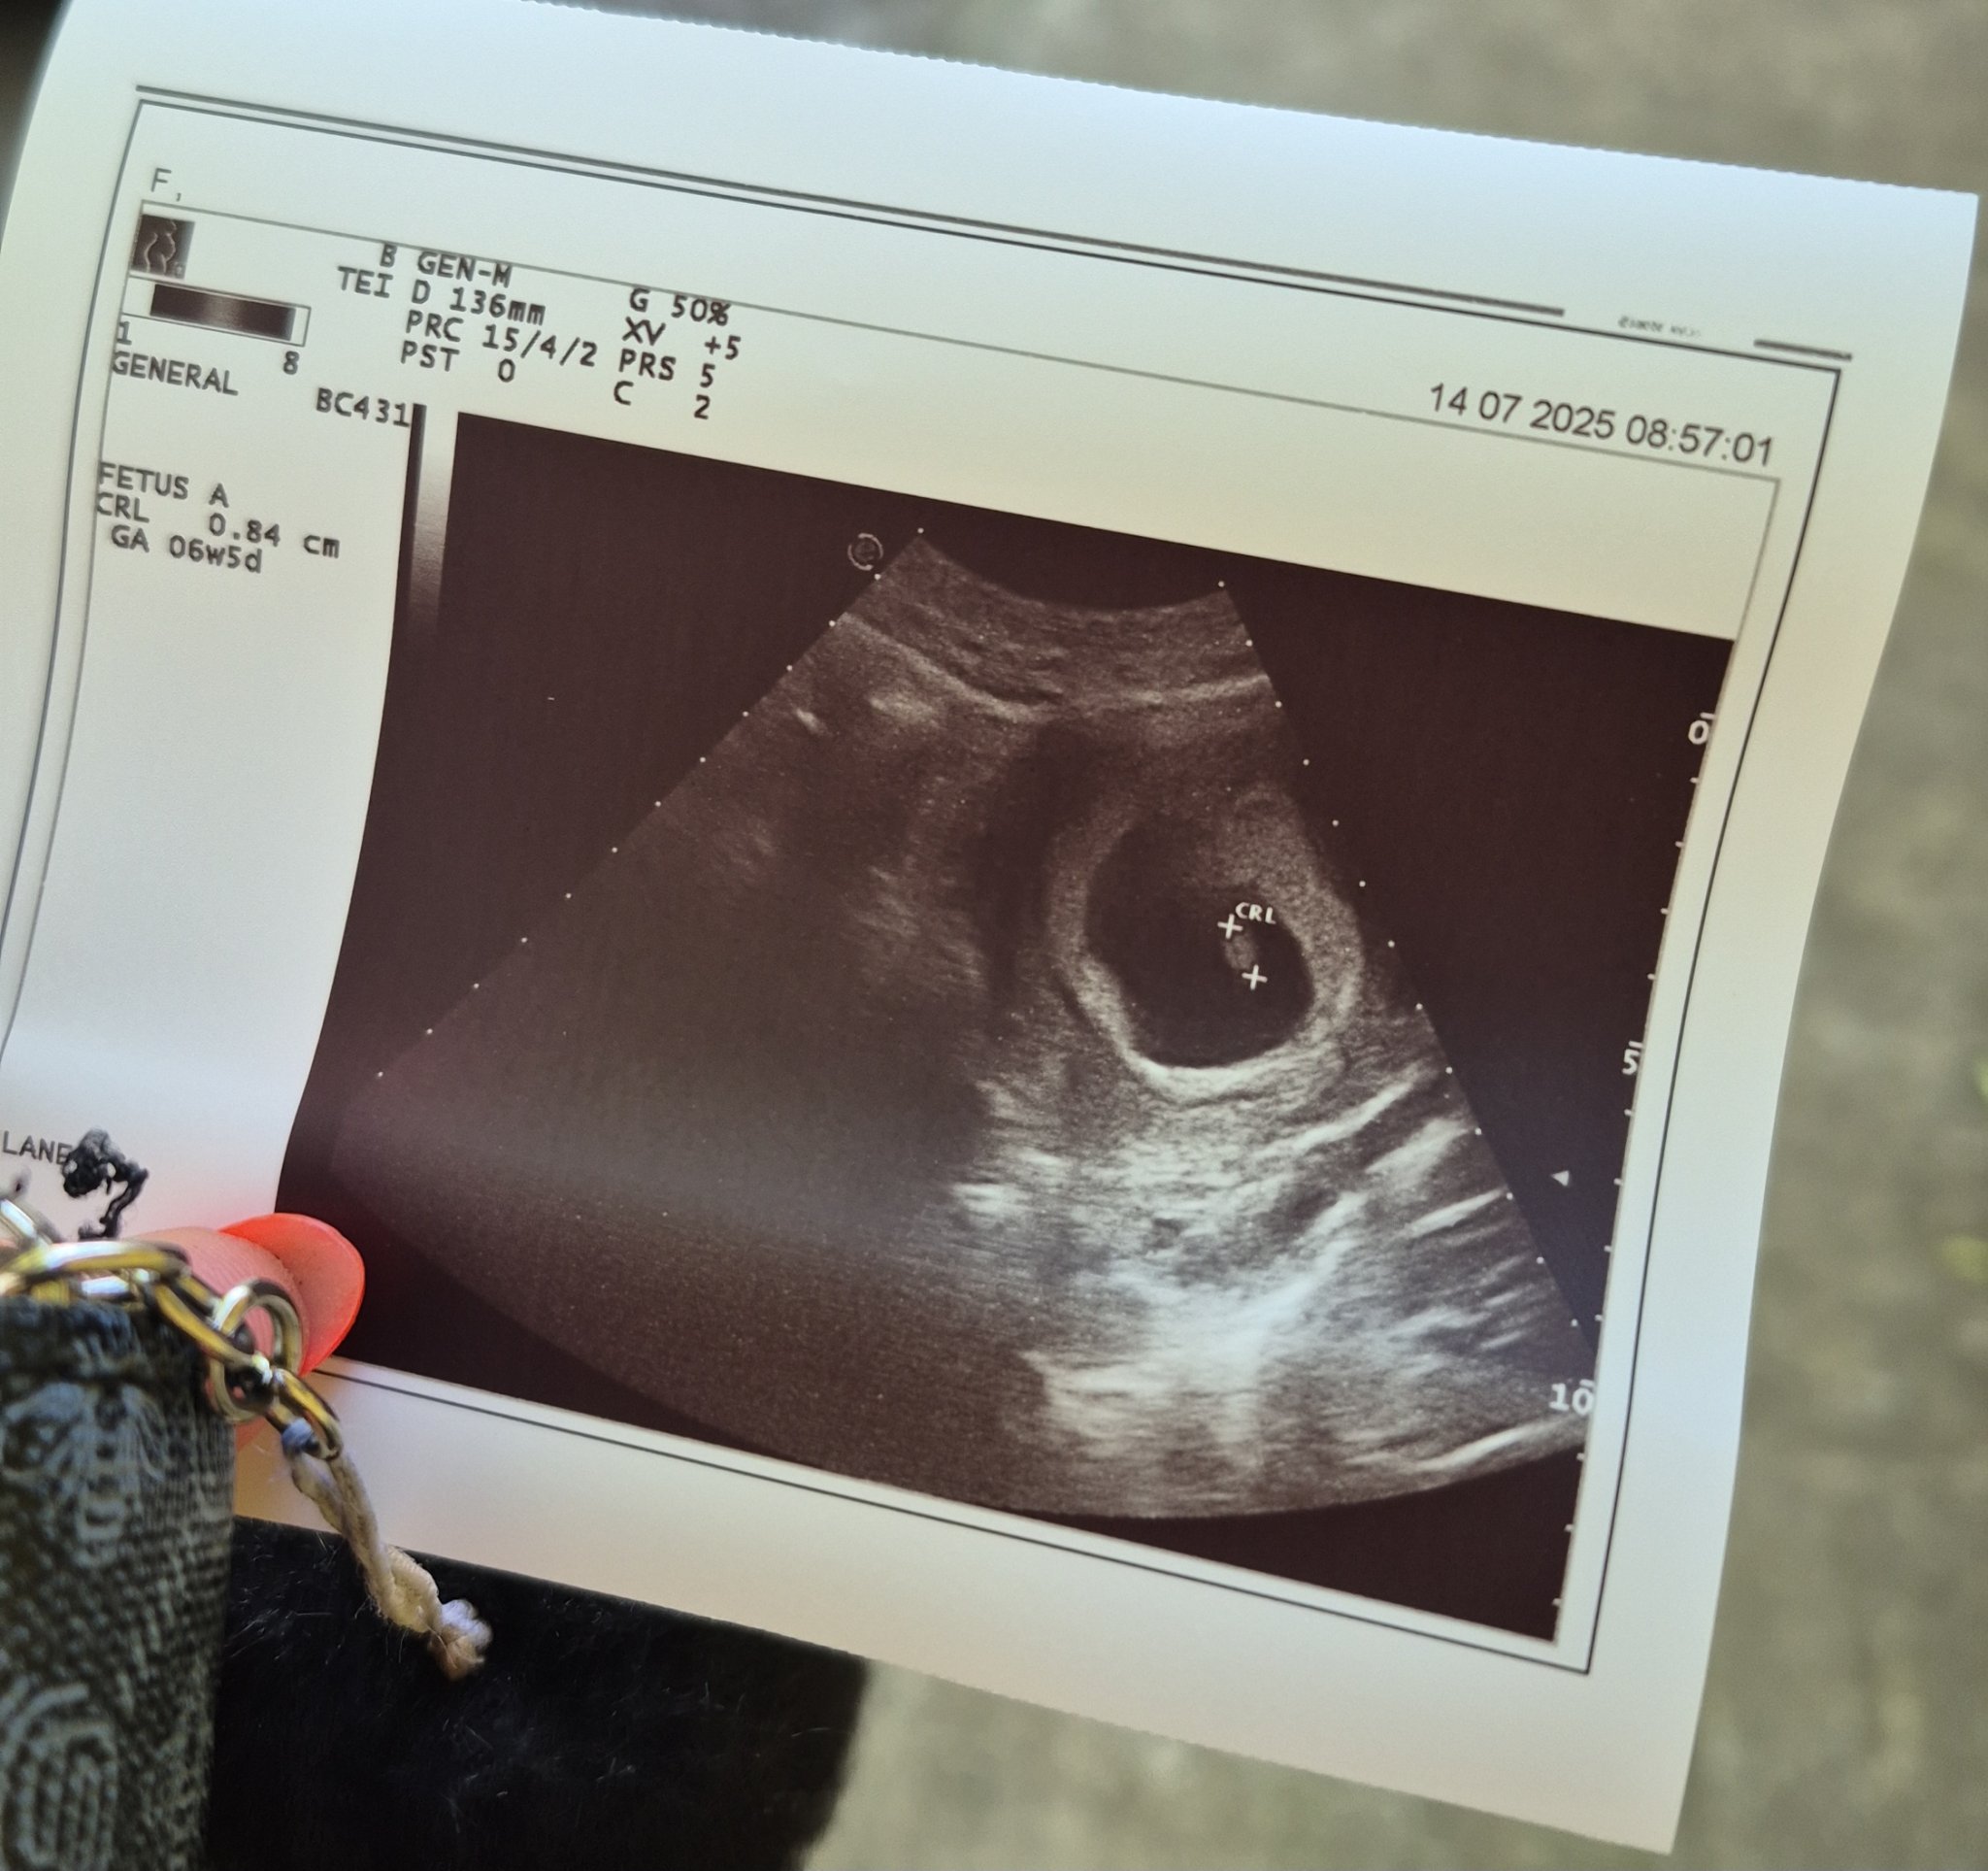

Здравейте, отново съм аз. Имам чувството, че всеки ден мога да ви пиша, тъй като много много се вълнувам. Тази сутрин отидох на преглед понеже много ме болеше корема и кръста, всичко е наред така ми казаха, болката била понеже съм вдигала нещо по-тежко и ми казаха да не вдигам нещо повече и да внимавам като се навеждам. Не ми казаха обаче в коя седмица съм, общо взето нищо не ми казаха. На първия преглед ми казаха, че съм в 5та г.с., по мои изчесления от датата на последния ми цикъл съм в 8 г.с + 1ден. Дадоха ми снимка но не разбирам на нея нещо дали пише

Stubbornh,на ехографската снимка се вижда,че сте в 6 г.с и 5 дни ,размерът на ембриона е 0.84 см.

Stubborn, кога е била последната ви менструация и овулацията потвърдена ли е с ехограф или лентички? Имате ли редовен цикъл и на колко дни е?

Ако сте 8+1 по ПРМ, а ембриона отговаря на 6+5 това е повече от седмица разлика. Или става въпрос за късна овулация и дълъг цикъл или наистина ембриона изостава. В 8+1 г.с. би трябвало да се види добре оформен ембрион и да се чуе пулс. На тази тема на по предните страници има снимка на една дама с нейния ембрион в 8+1 да сравните как трябва да изглежда. Другия вариант е овулацията да ви е закъсняла с една седмица. На предния път, когато са ви казали 5 г.с, вие в коя бяхте по календар?

По календар бях в 6 г.с.